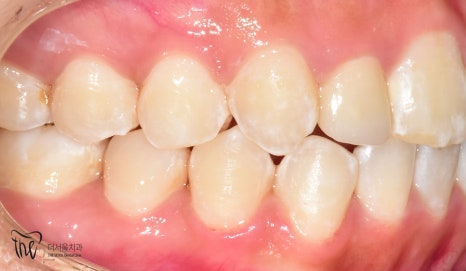

사진을 보면

*측절치에서 왜소치 가 관찰되고 있었으며

아랫니가 윗니를 덮고 있는 반대교합을 보였습니다.

측면에서 바라보면

송곳니가 튀어나온게 두드러졌으며

치열이 고르지 못하고

삐뚤빼뚤 한 것을 볼 수 있었습니다.